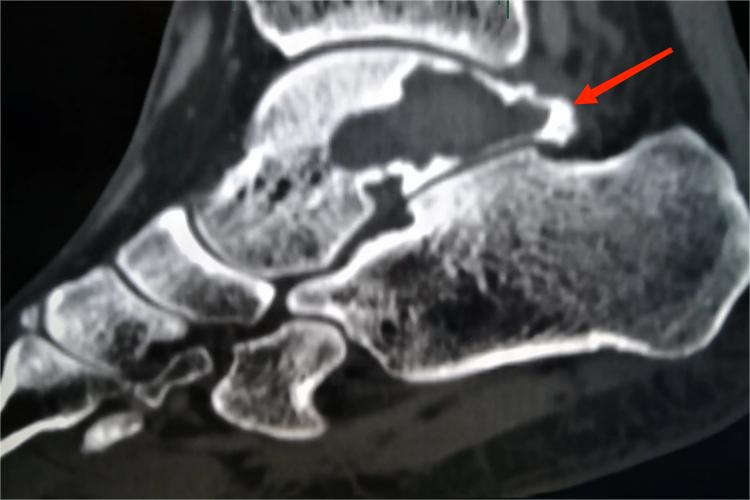

骨囊肿是在骨内形成的一个充满棕黄色液体或血清性物质的囊腔,可发生于距骨等处,X线见圆形或椭圆形界限清楚的溶骨性病灶,骨皮质有不同程度的膨胀变薄。患者多数无明显症状,有时局部有隐痛或肢体局部肿胀。